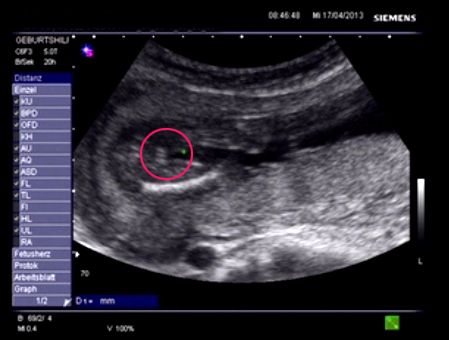

Hello Everyone! Its me again :-) A Gender swaying friend (wanting a Girl) made the The Baby Gender Predictor Test: Am I having a boy or girl? DNA - Test And it said -> BOY! Her second son is 19 Months old and she was pretty careful making the test... Now she went to her doctor’s appointment and the doctor was sure it’s a Girl!! What do you think? Picture 1 : (NT-Scan – Baby Nr.3 -> Is the current pregnancy ) Sohnemann 2 is her second Boy ;-) Picture 2: 17 weeks pregnant potty scan the arrow should show the girl parts .... So Ladys what do you think any chance itīs a GIRL??? Greetings & Thanks ....

Attachment 10346

Bauch= Belly

Bein = Leg

-> = Gender